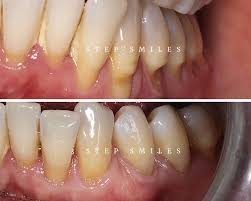

Gum surgery

Teeth cleanup

Gallery